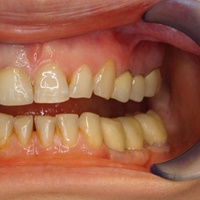

Pod koroną w moście rozwinął się proces zapalny obejmujący fiurkację dalszą zęba 26. Po radektomi wykonano nowy most, na tych samych zębach filar.